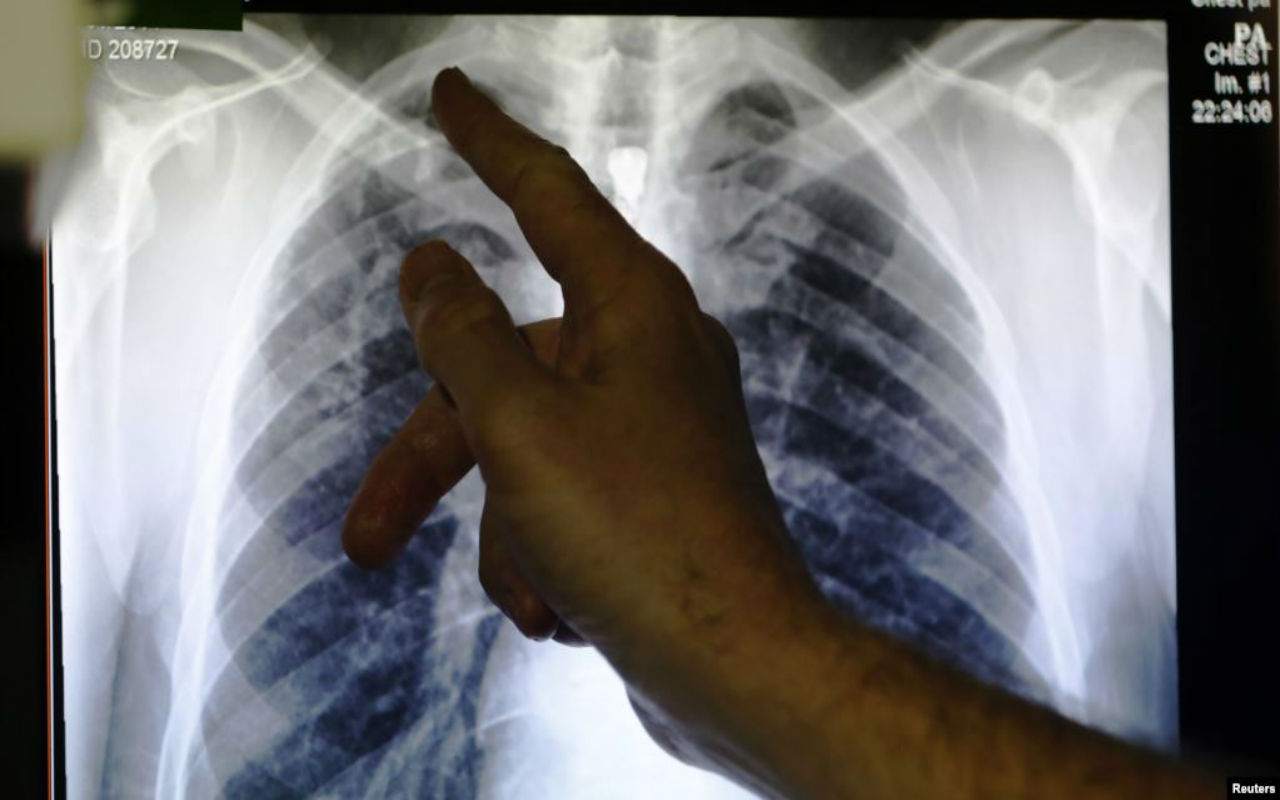

La Oficina de Aduanas y Protección Fronteriza de Estados Unidos (CBP) se niega a revelar públicamente cuántos migrantes que se encuentran en detención tienen enfermedades contagiosas, pese a que se han reportado brotes de gripe, tuberculosis y varicela, según un artículo de CNN.

Los médicos se encuentran preocupados desde hace mucho tiempo sobre estos entornos congestionados que dicen son caldo de cultivo para enfermedades graves.

“Crean instalaciones que fomentan la propagación de agentes infecciosos”, dijo el doctor William Schaffner, asesor de los Centros para el Control y la Prevención de Enfermedades (CDC) sobre cuestiones relacionadas con las vacunas.

“Hemos visto todo, desde paperas, varicela, influenza y tuberculosis”, escribió un portavoz de CBP en un correo electrónico a la agencia de noticias.